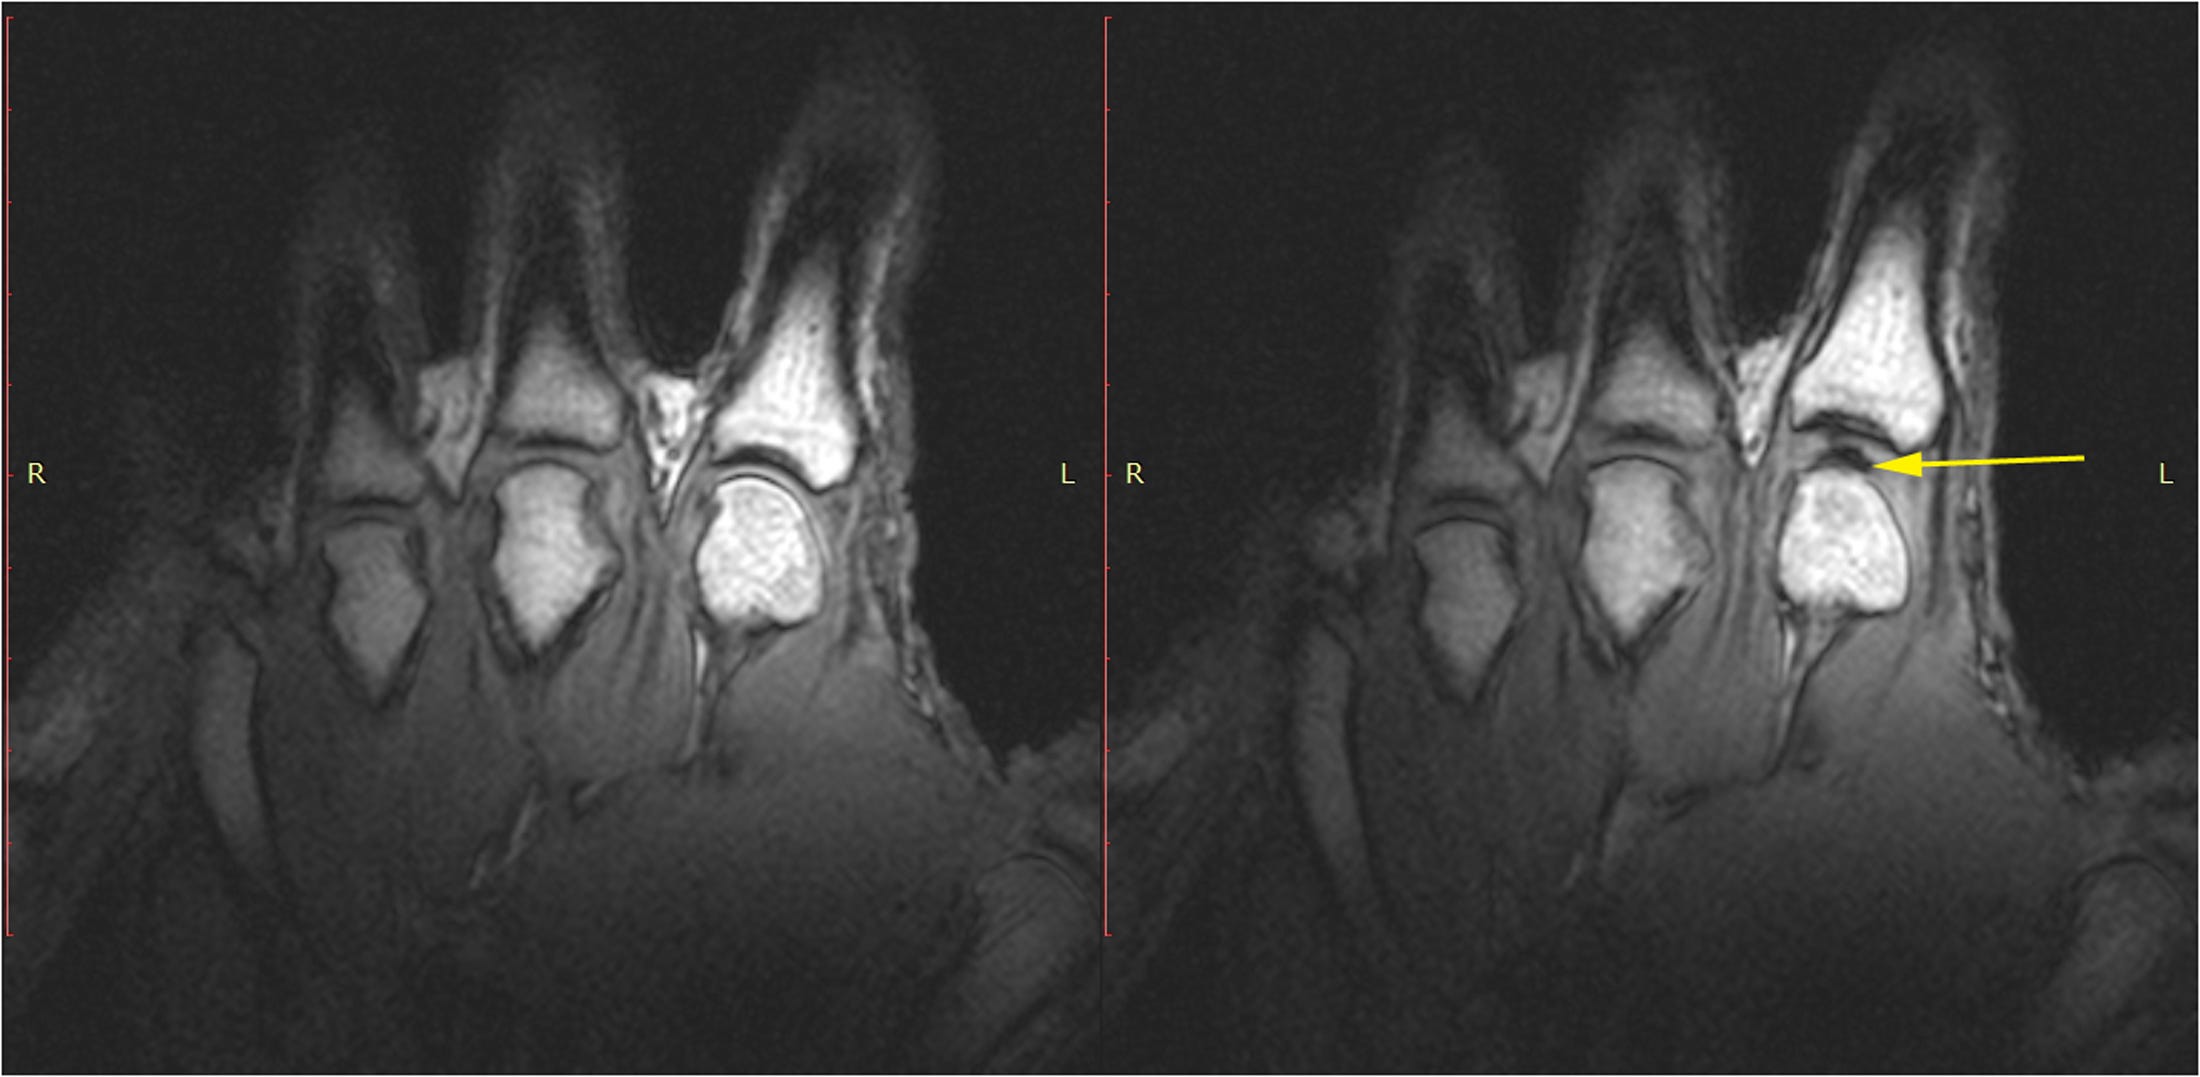

This may seem like menial work, but efforts to understand knuckle cracking pepper more than a hundred years of scientific literature, and continued into the 2000s. Then, in 2015, Canadian researchers watched knuckles cracking on MRI and were able to document ‘cavitation’, bubbles that pop open to fill space where a knuckle joint is stretched. Soon after, mathematical work confirmed those tiny bubbles can fully account for the impressive sound of a knuckle crack.